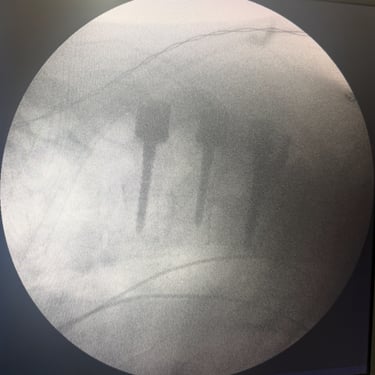

Tumor vertebral dorsal hemorrágico: descompresión medular, biopsia y artrodesis dorsal

El tumor vertebral dorsal puede ocasionar compresión de la médula espinal, dolor intenso y alteraciones neurológicas progresivas. En algunos casos, estos tumores presentan componente hemorrágico que incrementa la presión sobre las estructuras nerviosas. El tratamiento quirúrgico puede incluir descompresión medular para liberar la médula espinal, toma de biopsia para establecer el diagnóstico histopatológico y artrodesis dorsal con instrumentación para estabilizar la columna vertebral. Este abordaje permite reducir el riesgo de daño neurológico, aliviar los síntomas y mantener la estabilidad vertebral. La cirugía se realiza con técnicas especializadas que buscan preservar la función neurológica y mejorar la calidad de vida del paciente.